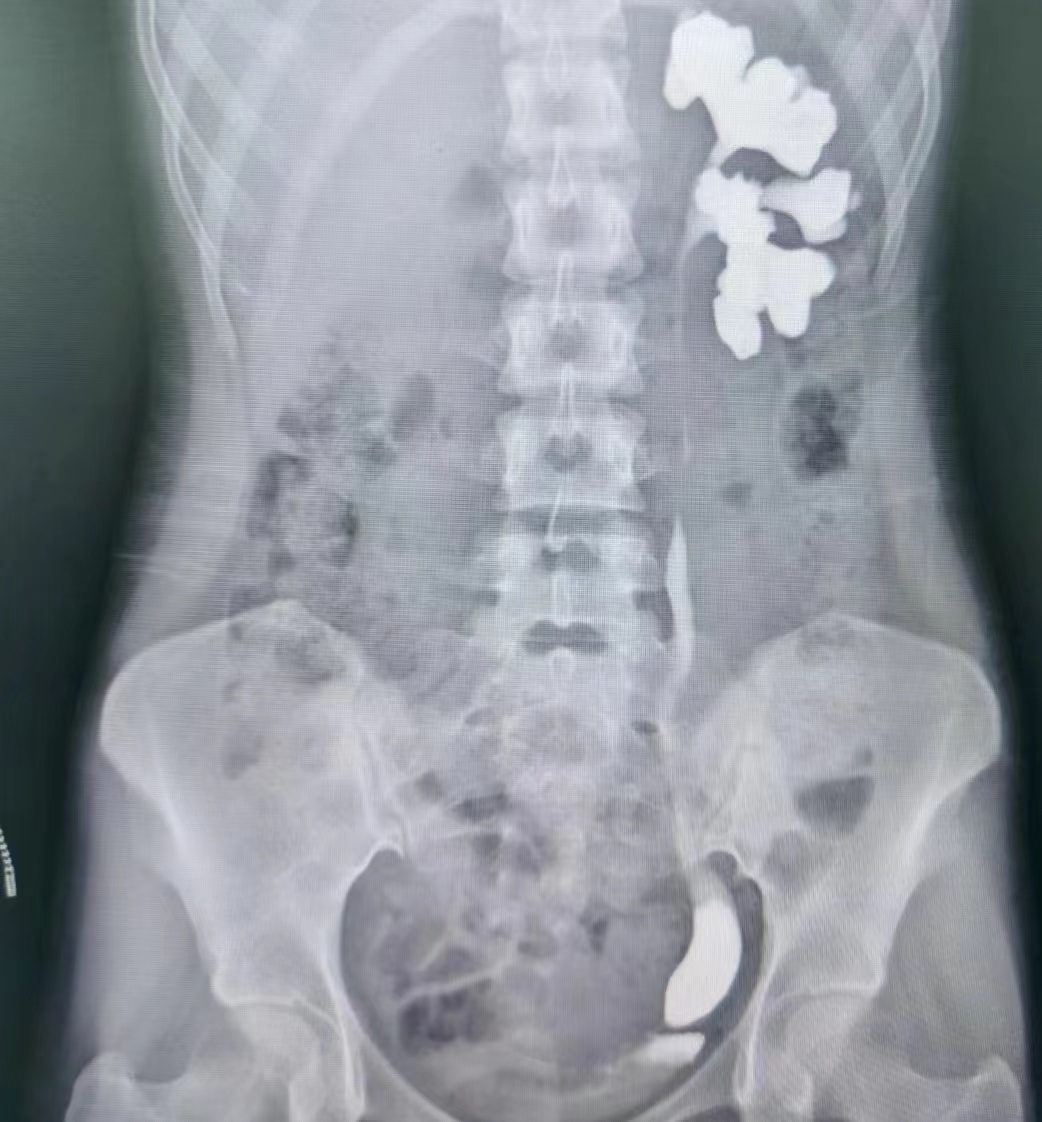

患者21岁,某高校学生,一月前因左侧腰背部疼痛不适在当地医院就诊,行泌尿系B超提示左肾积水伴左侧输尿管末段狭窄。医生建议其行手术治疗,考虑到术后需要家人照顾,患者便回到渭南,来到市中心医院泌尿外科就诊。

蔡高飞主任医师和王增利副主任医师诊疗组将患者收住入院,入院后行静脉肾盂造影和逆行肾虚输尿管造影提示左侧输尿管末端狭窄。科主任赵卫红立即组织全科讨论,由于输尿管下段走行毗邻髂血管和子宫动脉和卵巢、输卵管,术中稍有不慎损伤髂血管则会引起大出血,损伤子宫附件则会影响生育功能。考虑到患者年龄较小,本着手术效果和术后美观的原则,根据本科室近年来在腹腔镜手术方面的积累,决定为其实施腹腔镜下输尿管再植术,此手术方式创伤小,出血少,术中视野好,术后恢复快。